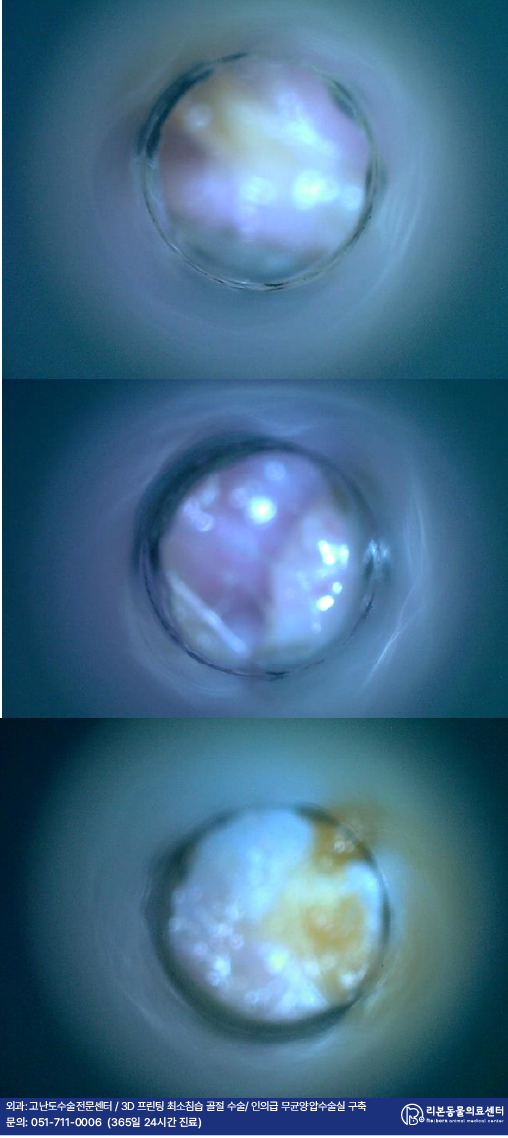

외이도 검사 상 환자의 귀는 발적과 농성 귀지가 잔뜩 들러붙어 있었습니다.

관찰되는 귀지를 채취하여 진행된 도말 검사 상에서는 좌측 귀의 세균 감염, 우측 귀의 진균과 세균의 동시 감염이 관찰되었습니다.